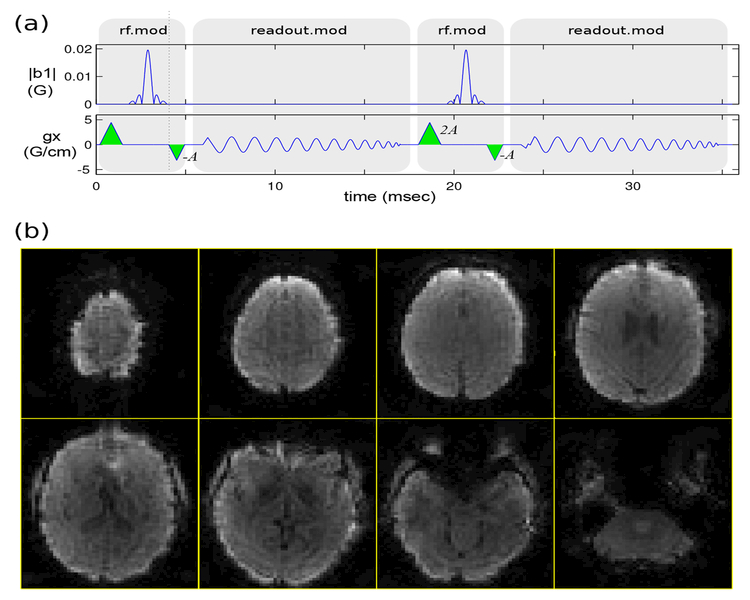

Figure 4:

Rapid whole-brain dynamic T2*-weighted imaging using 3D stack-of-spirals PRESTO. Each 72×72×54 image volume was acquired in 2.9 sec (fully sampled). (a) Pulse sequence diagram (gy, gz waveforms not shown). Echoes were shifted by one TR by placing trapezoidal gradients (green) with area −A and 2A just before and after the spiral-in readout, respectively, with the net gradient area A corresponding to two cycles of phase across the voxel along both x and y dimensions. (b) Reconstructed image volume for one time-frame (only eight of the 54 slices are shown), showing strong T2*-weighting as expected.

Figure 4(b) shows a representative result from the stack-of-spirals PRESTO imaging experiment. Lower slices exhibit signal loss near the frontal sinus and ear canals which is evidence of strong T2*-weighting as desired.